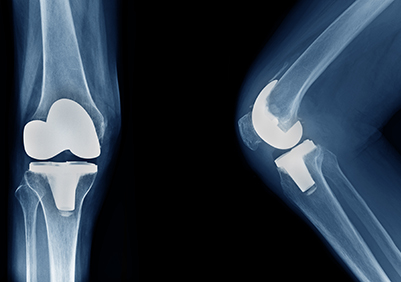

Joint Replacement

If you suffer from restricted mobility or joint pain you may be a candidate for joint replacement surgery.

Knee Replacement

If you suffer from restricted mobility in the knee, you may be a candidate for knee replacement surgery.